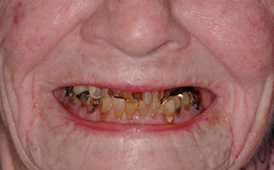

Fig 8. Failing dentition in an 82-year-old patient currently diagnosed with tardive dyskensia.

Figure 8

Fig 12. Treatment to restore this patient’s smile and functionability commenced when she was 102 years old.

Figure 12

This is an unfortunate mindset in that current advances in protocol and technology can result in significant advantages in addressing some or most of these concerns. The patient shown in Figure 12 may serve to illustrate this point. She had a destroyed maxillary dentition, a less-compromised but highly unesthetic mandibular component, and a single goal: to be able to "smile at my grandchildren again." In consultation with her and her family, it was decided that a double-arch fixed implant approach would most realistically address her esthetic goals and provide her with the desired prosthetic result. She was 102 years old at the time of initial consultation. Using a staged operating-room approach, provisional restorations were initially delivered, followed by subsequent definitive hybrid final restorations. She was able to use these comfortably for the next 6-½ years (Figure 13 and Figure 14).